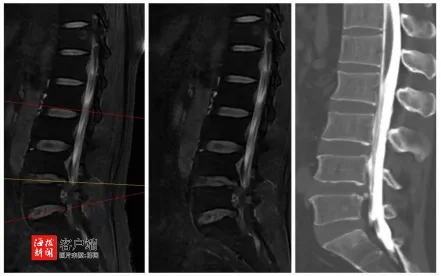

在仔细询问了李奶奶的病史后,孟教授又进行了一次全面而细致的体格检查,力求不错过任何可能导致疼痛的线索。经过深入的诊断,孟教授凭借他敏锐的医学洞察力,明确李奶奶患有腰椎椎管狭窄症,并用浅显易懂的语言,向李奶奶详细解释了她的病情,描述了腰椎椎管狭窄症的影响,以及它如何成为李奶奶长期疼痛的根源。

面对治疗方案的选择,孟教授提出了一项创新的微创手术——计算机导航下行斜外侧入路腰椎融合术。这种手术不仅能有效地缓解李奶奶的疼痛,还能恢复腰椎的稳定性。且手术创伤小,恢复期短。